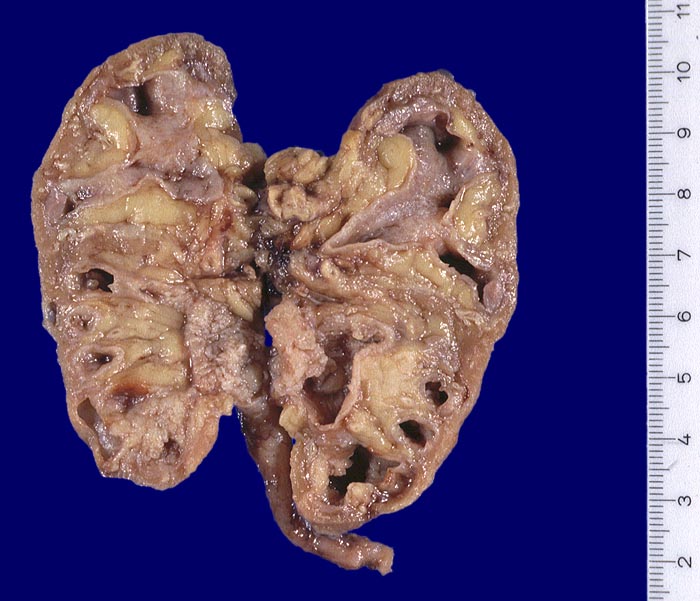

AP/ Analgetikanephropathie

Analgetikanephropathie

Niere

Makroskopie